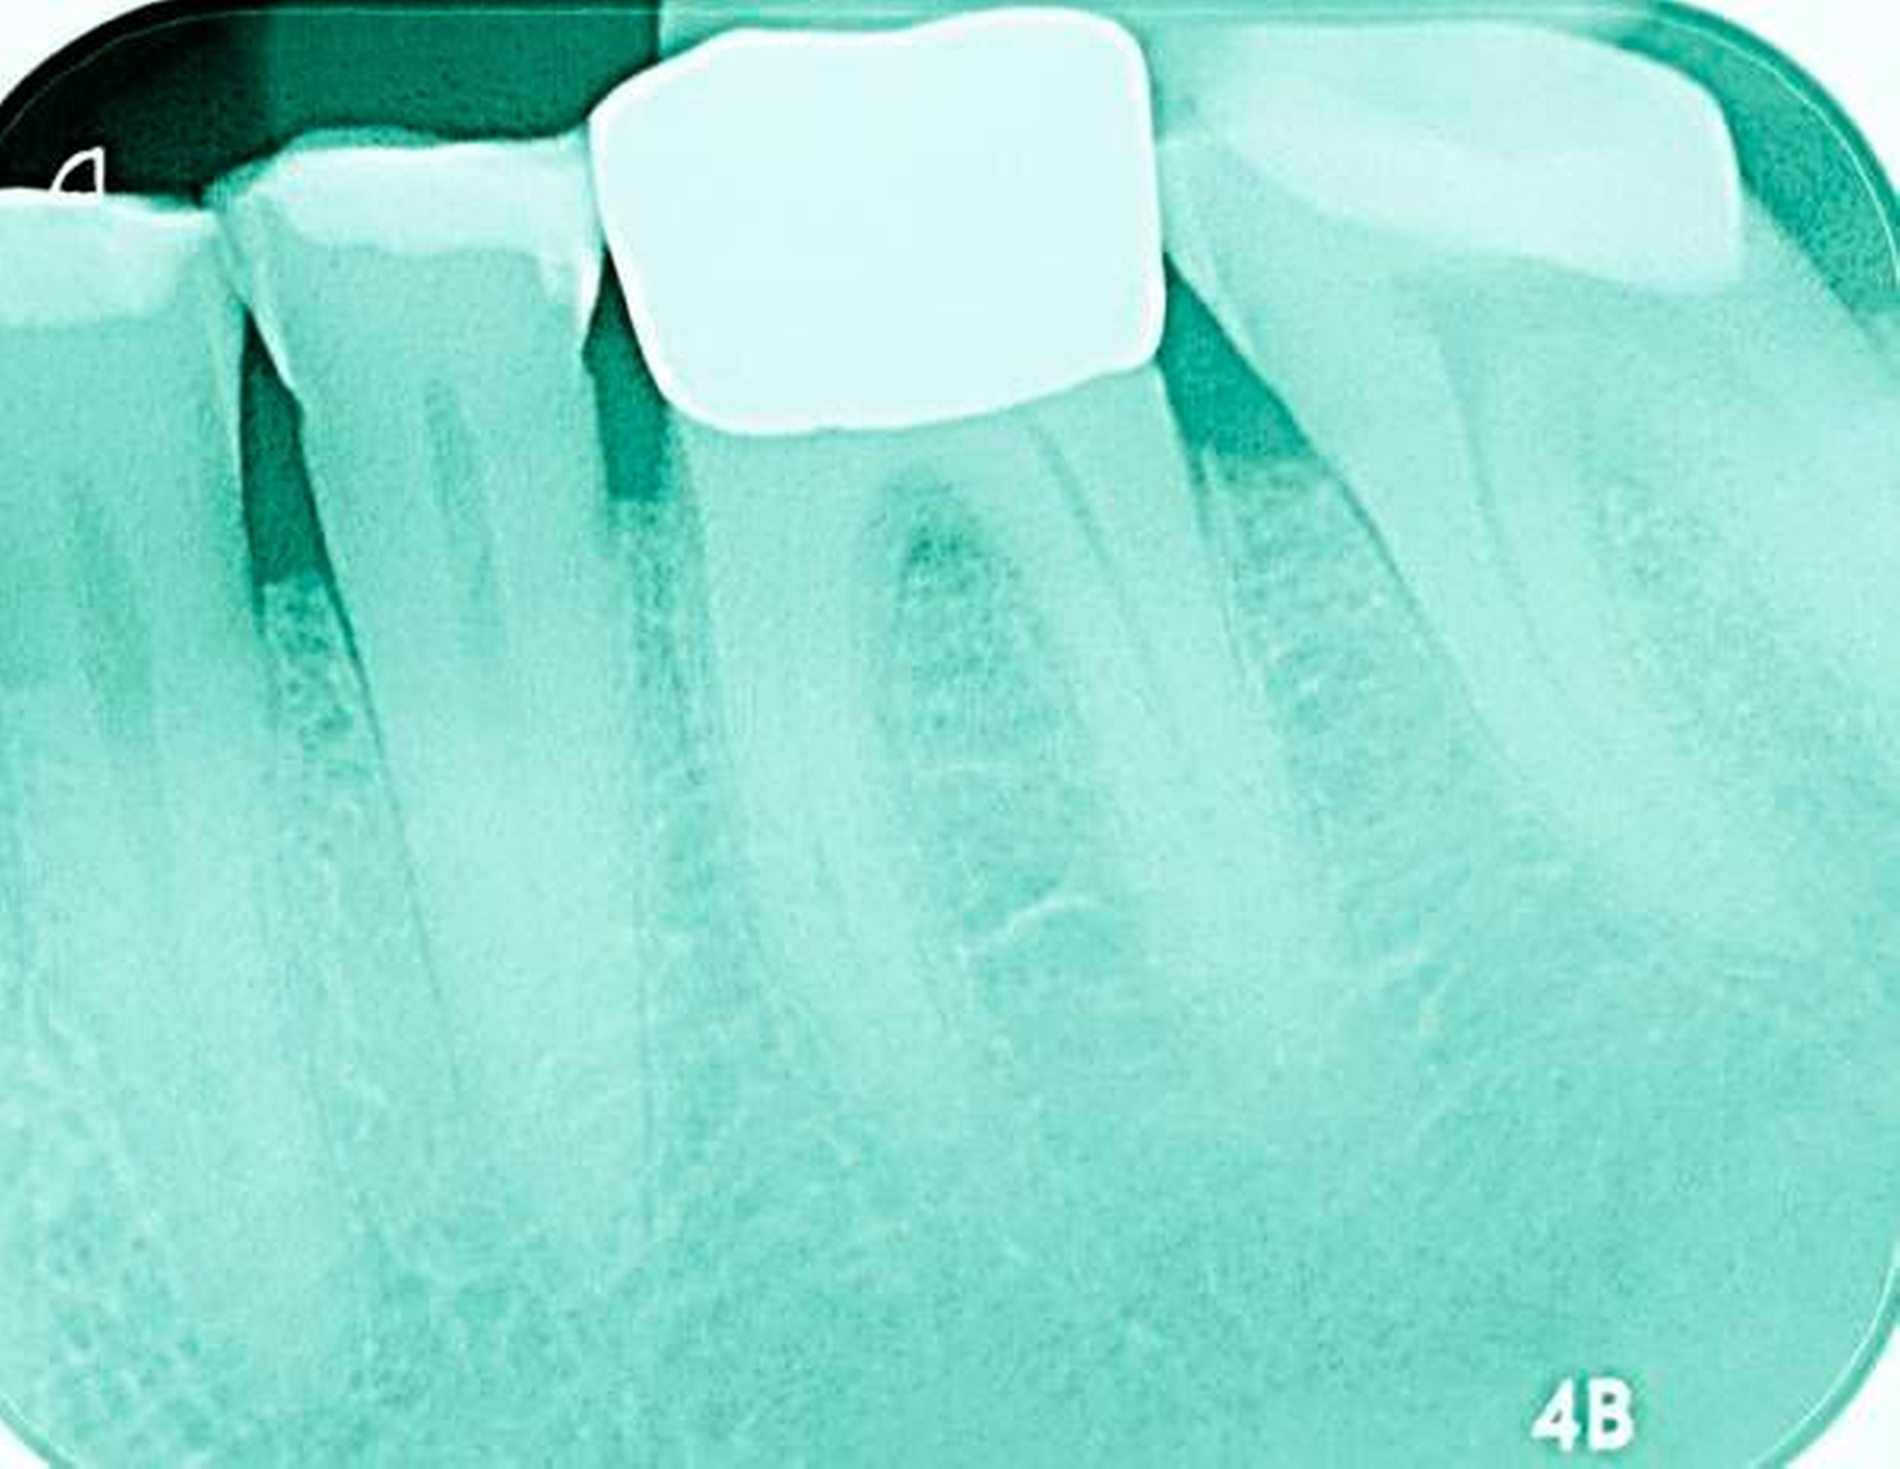

Abbildung 3: ausgedehnte Kronen- und Wurzelkaries unter einer Krone am Pfeilerzahn 47 einer seit Jahrzehnten eingegliederten Brücke von 45–47 bei einer 71-jährigen Patientin, die nach einer zerebrovaskulären Erkrankung unter Antikoagulantientherapie steht, vor etwa zwei Jahren hat sie eine Umstellung auf eine fluoridfreie Zahnpaste vorgenommen.

3. Restaurative Versorgungen bei Wurzelkaries

Freiliegende Wurzeloberflächen können im Alter ein locus minoris resistentiae für Karies sein. Im Zusammenspiel ungünstiger Ernährungsgewohnheiten, nachlassender Mundhygiene sowie Änderungen von Speichelquantität und -qualität kommt es zuweilen zu einem präventiv und restaurativ schwer beherrschbaren Auftreten von Wurzelkaries. Gut zugängliche Kariesläsionen können mit einphasig eingebrachtem Komposit (R1-Restaurationen) angegangen werden (Abbildungen 3 bis 5). Bei schwerer zugänglichen Arealen kommt ein zweiphasiges Vorgehen in Betracht (R2-Restaurationen). Das Vorgehen bei der R1- und bei der R2-Technik wurde mehrfach beschrieben [Frese et al., 2014a, b, c, d; Staehle et al., 2014, 2017]. Im Fall von zirkulärer Wurzelkaries sollte frühzeitig eingegriffen werden, da ansonsten die gesamte Zahnkrone frakturieren kann.